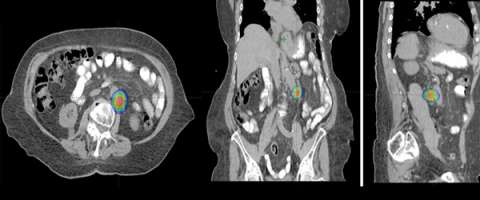

The second row shows images (axial, coronal, and sagittal) of the distribution of the radiation dose that was delivered to this area. One can see that the dose of radiation to this target is very tightly distributed to avoid as much normal tissue as possible.